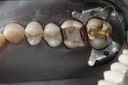

Gary Umeda #3 - 4 prep